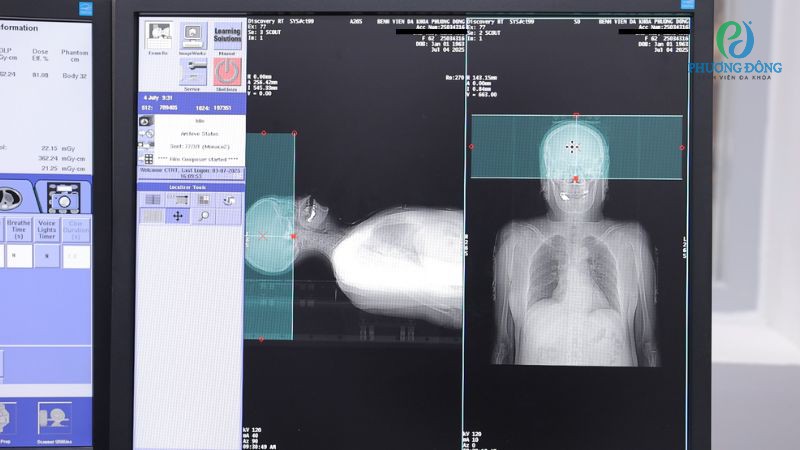

- Lập kế hoạch chi tiết (còn gọi mô phỏng): Những kỹ thuật chẩn đoán hình ảnh như CT, MRI sẽ được ứng dụng để xác định vị trí và kích thước khối u. Đồng thời, một mặt nạ hoặc khuôn cố định cá nhân sẽ được thiết kế để giữ đầu bệnh nhân luôn ở đúng vị trí.

- Trước khi chiếu xạ: Sau khi đã xây dựng phác đồ điều trị phù hợp, tùy theo thể trạng, vị trí và kích thước u não mà bệnh nhân sẽ được thông báo về số buổi xạ trị. Trước khi chiếu xạ, kỹ thuật viên sẽ điều chỉnh tư thế khi người bệnh nằm trên máy gia tốc tuyến tính.

- Quá trình xạ trị: Xuyên suốt thời gian xạ trị bệnh nhân cần nằm yên trên bàn điều trị, hạn chế tối đa cử động dẫn đến nguy cơ tác động sai lệch. Kỹ thuật viên xạ trị sẽ giám sát toàn bộ quá trình từ phòng điều khiển, đảm bảo tính an toàn và hiệu quả.

Quy trình kỹ thuật thực hiện xạ trị VMAT cho bệnh nhân ung thư não tại Bệnh viện Đa khoa Phương Đông

Trung bình một buổi xạ trị VMAT chỉ kéo dài 20 phút, trong đó phần lớn thời gian dùng để điều chỉnh vị trí nằm, thời gian phát tia thực tế chỉ chiếm 2 - 3 phút. Kết thúc, bệnh nhân có thể xuất viện ngay trong ngày và không cần cách ly với mọi người.